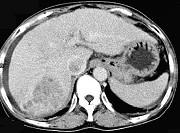

问题 女性,55岁,曾患乙肝,肝硬化多年,右上腹胀痛1月余,CT检查如图所示,最可能的诊断是 ( )

选项 A.肝硬化腹水、下腔静脉血栓形成 B.肝硬化腹水、胆管细胞癌 C.肝硬化腹水、肝癌并下腔静脉癌栓 D.肝硬化腹水、肝脓肿 E.肝硬化腹水、肝血管瘤

答案 C